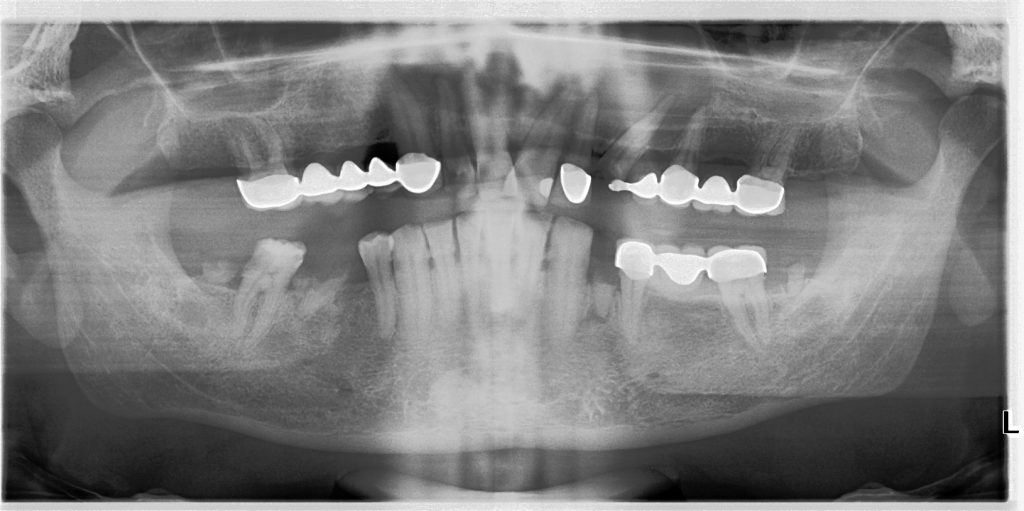

Diş kaynaklı ve diş kaynaklı olmayan olmak üzere ikiye ayrılmaktadır.

Diş kaynaklı olanlar, dişin oluşumu ve diş yapısının gelişimi esnasında rol alan hücrelerin anormal bir şekilde büyüyüp genişleyerek içerisinde hava, sıvı ya da cerahat içeren patolojik (sağlıksız) boşluklardır. Diş kaynaklı olmayanlar, çeneler ve yüz iskeletinin oluşumu esnasında anormal hücre göçleri ya da anormal hücre çoğalmaları sebebiyle oluşurlar.

Kistin büyüklüğüne ve agresifliğine göre lokal anestezi ya da genel anestezi altında cerrahi olarak kistin çıkarılmasıdır.